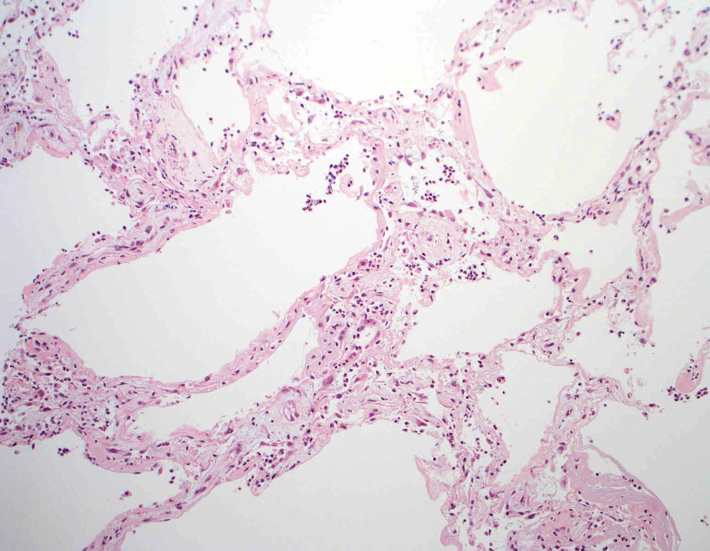

肺毛細血管炎 capillaritis

肺胞壁に多数の好中球浸潤。肺胞腔内に出血。 capillaritisが起こるWegener' granulomatosis劇症型には, なかなか肉芽腫性病変を見つけることは難しい

capillaritisの組織所見*17

Fig.01 capillaritisと肺胞出血Fig.02 Fig.01拡大像